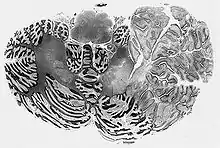

| Dysplastic cerebellar gangliocytoma histology | |

MICROSCOPY (lhermitte-duclos disease) 1>Enlarged circumscribed cerebellar folia 2>internal granular layer is focally indistinct and is occupied by large ganglion cells 3>myelinated tracks in outer molecular layer 4>underlying white matter is atrophic and gliotic

In Lhermitte–Duclos disease, the cerebellar cortex loses its normal architecture, and forms a hamartoma in the cerebellar hemispheres. The tumors are usually found on the left cerebellar hemisphere, and consist of abnormal hypertrophic ganglion cells that are somewhat similar to Purkinje cells. The amount of white matter in the cerebellum is diminished. Like cowden syndrome, patients with Lhermitte–Duclos disease often have mutations in enzymes involved in the Akt/PKB signaling pathway, which plays a role in cell growth. Mutation in PTEN gene on chromosome no. 10q leads to increased activity of AKT and mTOR pathways.[3]